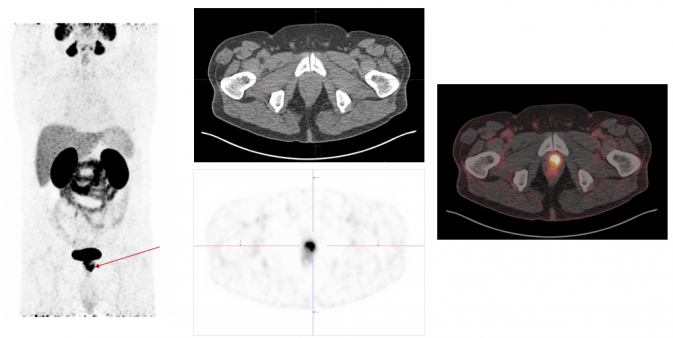

Exemplary case study on PSMA-PET/CT diagnostics:

PSMA.png